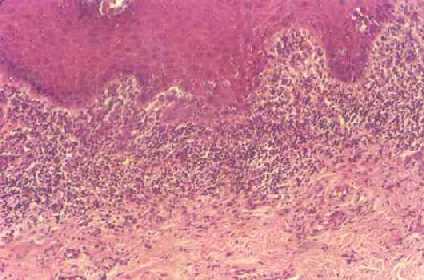

¿Que es el Liquen Plano?

El liquen plano es una enfermedad poco común que causa erupción o lesión inflamatoria y picazón recurrentes en la piel o en la boca. No se conoce la causa exacta de esta enfermedad, pero es probable que esté relacionada...